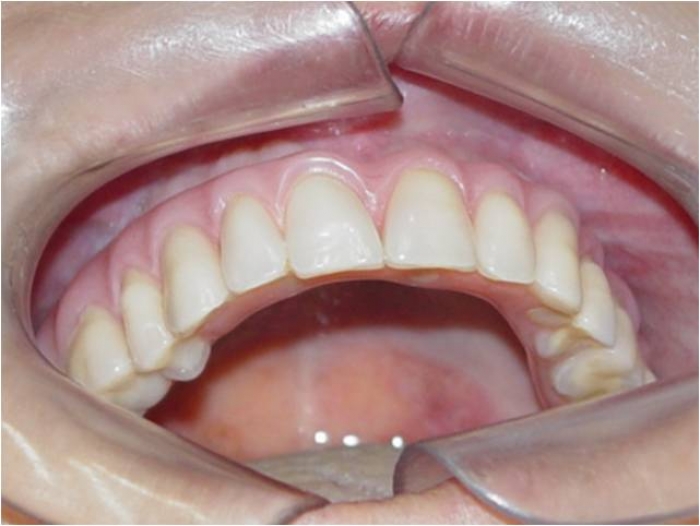

Prótese fixa em resina sobre implantes, do caso terminado em Dezembro de 2007